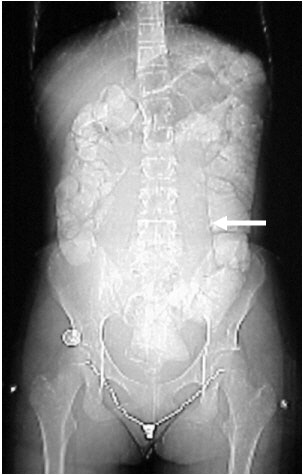

In Figure CT 9, the scout film shows a gaseous abdomen with displacement of bowel contents towards the right lower quadrant.

Axial images (Figures CT 10 and CT 11) show a mass beginning just below the kidneys on the left side and extending almost through the pelvis. The child was diagnosed with Wilm’s tumor of the left kidney.